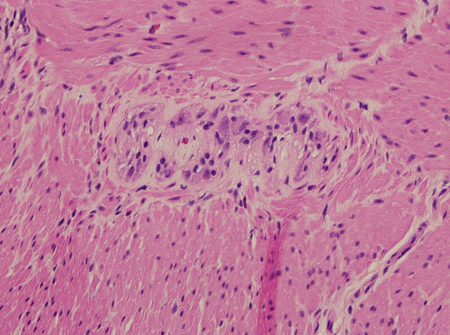

A patologia da biópsia retal mostrará ausência de células ganglionares na doença de Hirschsprung. Também pode mostrar a presença de nervos hipertróficos (maiores que 40 micrômetros em uma criança com menos de 6 meses), mas isso pode estar ausente em pacientes com doença de segmento longo ou aganglionose colônica total (ACT).[53] Outras colorações imuno-histoquímicas, incluindo calretinina, transportador de colina e acetilcolinesterase, podem ser marcadores auxiliares úteis.[53][54]

[Figure caption and citation for the preceding image starts]: Hematoxilina e eosina mostrando células ganglionares no plexo mioentéricoDa coleção pessoal da Dra. Lily Cheng; usado com permissão [Citation ends].